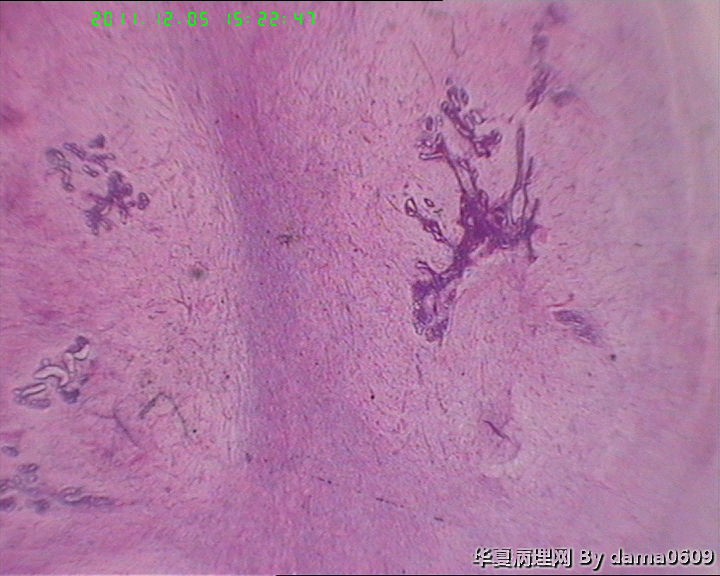

肿物一:镜下见乳腺小叶结构紊乱,小叶内、小叶间间质增生,构成肿瘤主质。增生间质呈梭形细胞样,细胞稀疏、异性不明显,其间见大量胶原纤维,小血管增生,局灶有红细胞渗出。见到一处导管大汗腺化生。

肿物二:镜下呈结节状,结节以导管或小叶为中心,围以增生的间质成分,梭形细胞构成,稀疏,增生的血管呈“鹿角状”。大结节内见局灶间质有出血或红细胞外渗,局灶导管内间质增生呈乳头/分叶状,上皮下无密集增生的间质细胞。结节大小不等,以窄带样纤维细胞束彼此分隔,互不融合,纤维细胞束细胞密集,内有增生的小血管。